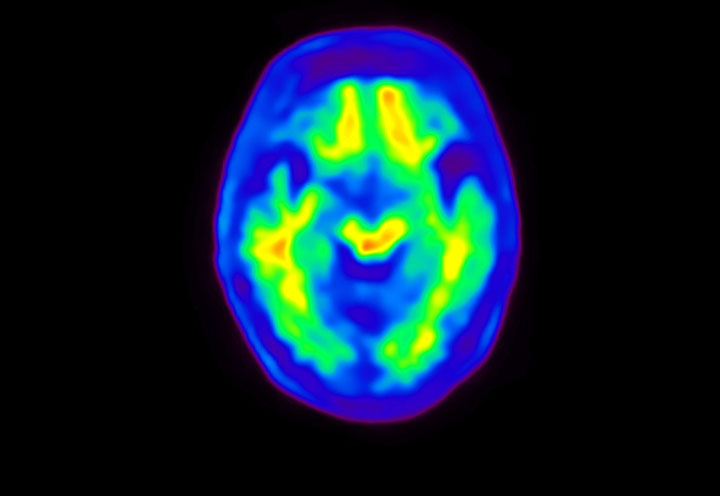

Head / Case4 : Amyloid

Sagittal

Courtesy : Kindai University Hospital

- Imaging protocol

- Injected dose: 3.21 MBq/kg, 18F-Flutemetamol

- Uptake time: 100 minutes

- Scan time: 20 minutes